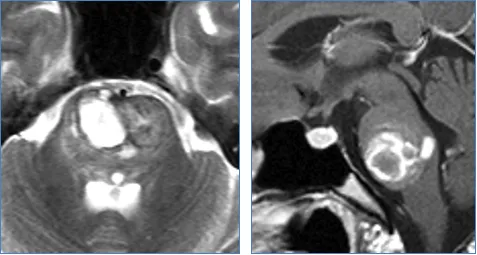

桥脑海绵状血管瘤病变位置,血管病变不邻接桥脑表面,但它单侧移动周围的固有结构,包括外展神经和面神经。

1、如果损伤到展神经核,可能会出现斜视;

2、如果损伤到面神经核,可出现面瘫;

3、如果出现三叉神经核损害,可出现损伤侧面部感觉异常;

4、如果损伤到下行神经传导,患者可出现瘫痪、偏瘫等症状;

5、如果导致严重脑干损害,还可能会导致唿吸、心跳改变等。